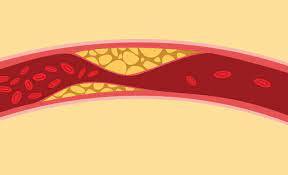

علاوه بر حمله قلبی، عوارض جدی دیگری نیز در اثر عدم درمان کلسترول “بد” وجود دارد.

تصلب شرایین، که تجمع پلاک در سراسر بدن است

- بیماری شریان کاروتید

- بیماری عروق کرونر قلب

- بیماری شریان محیطی

- سکته مغزی

- ایست قلبی ناگهانی

برخی افراد ممکن است به دلیل عوارض کلسترول بالای طولانی مدت به دارو یا جراحی نیاز داشته باشند.